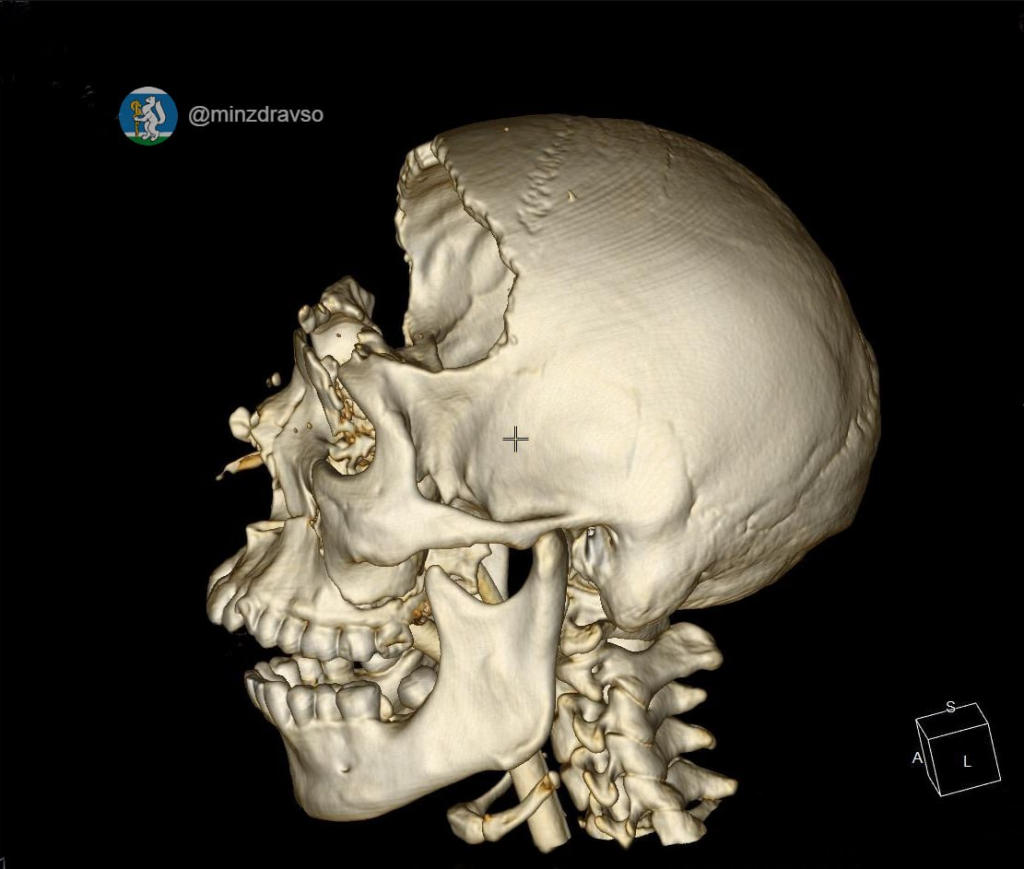

Специалисты Городской больницы №1 Нижнего Тагила спасли 25-летнего мужчину, который попал в ДТП. Он получил тяжёлые травмы головного мозга, множественные переломы костей черепа, особенно пострадали основание черепа и лобная кость. Благодаря профессионализму врачей учреждения здравоохранения и современному оборудованию, введённому в эксплуатацию в рамках нацпроекта «Продолжительная и активная жизнь», мужчина смог встать на ноги.

Серьёзная авария на уральской дороге едва не стоила жизни 25-летнему мужчине — с раздробленным черепом его экстренно госпитализировали в Городскую больницу №1 Нижнего Тагила. Ситуация осложнялась кровотечением и риском инфицирования головного мозга.

Высокоточный компьютерный томограф, имеющийся в медучреждении, позволил врачам быстро установить диагноз и выбрать тактику лечения. Нейрохирурги провели операцию, которая длилась около 2,5 часа. Они применили сложную методику — бифронтальную трепанацию, при которой обеспечивается расширенный доступ к головному мозгу и минимизируются его повреждения, остановили кровотечение, ювелирно удалили гематомы объёмом около 50 миллилитров, провели герметичную пластику мозговой оболочки. Оперативное вмешательство позволило избежать тяжёлых неврологических осложнений и спасти жизнь пациента.